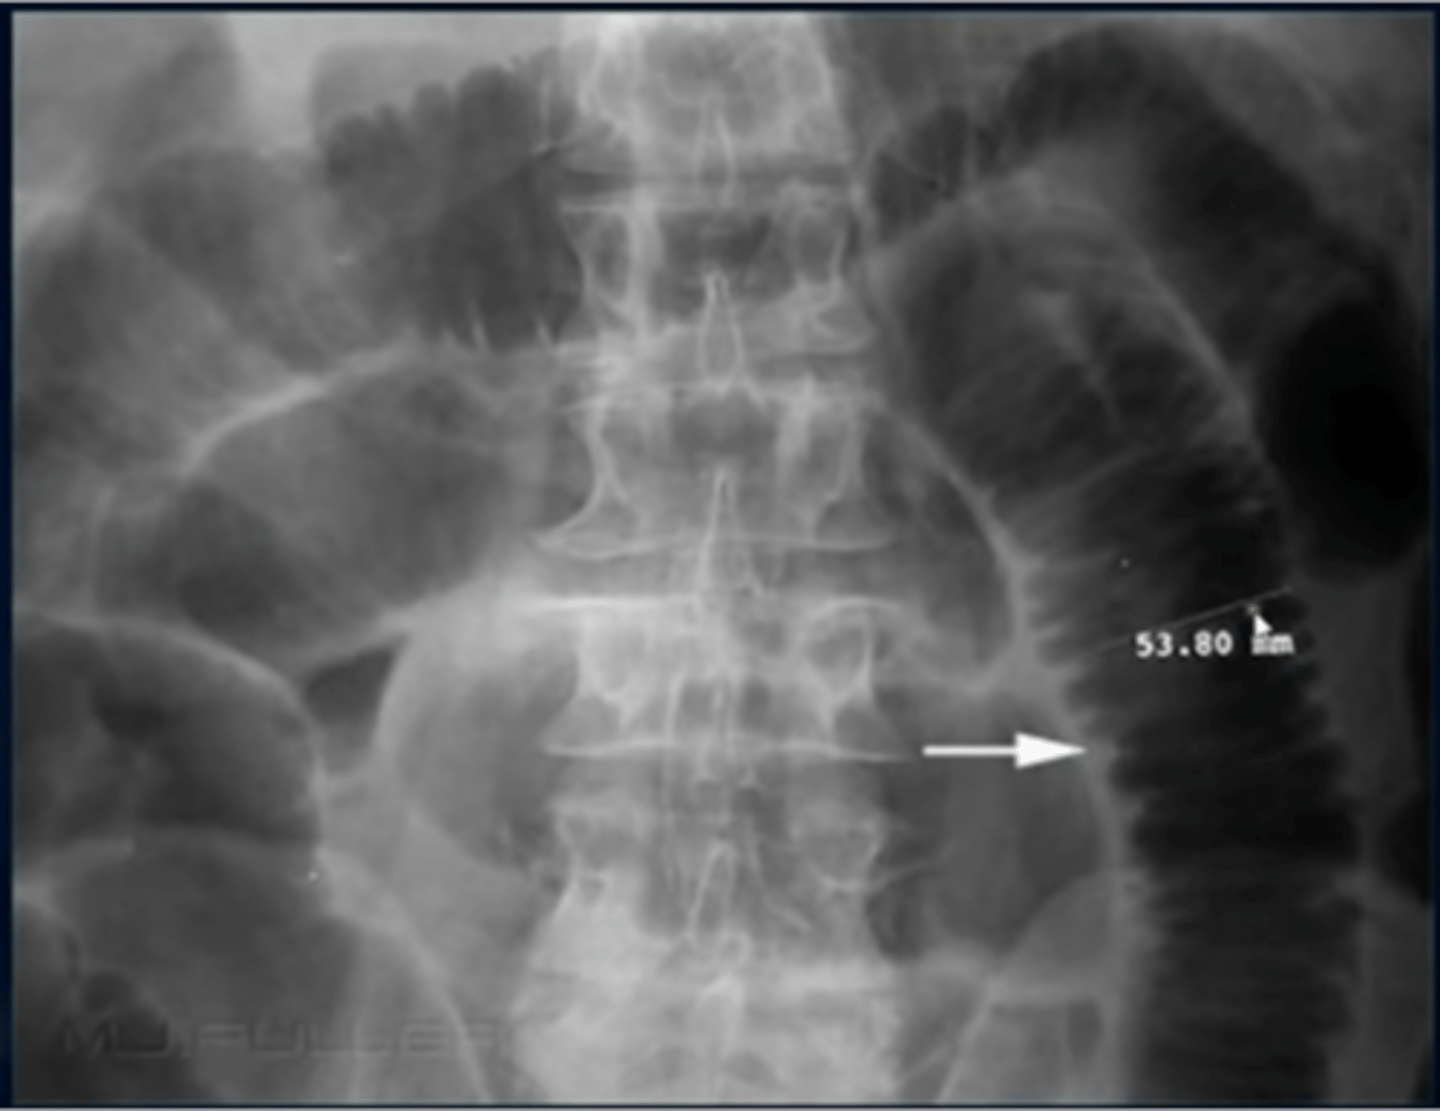

Abdominal aortic aneurysm calcification (pic 2)

Abdominal aortic aneurysm calcification (pic 3)

Abdominal aortic aneurysm calcification